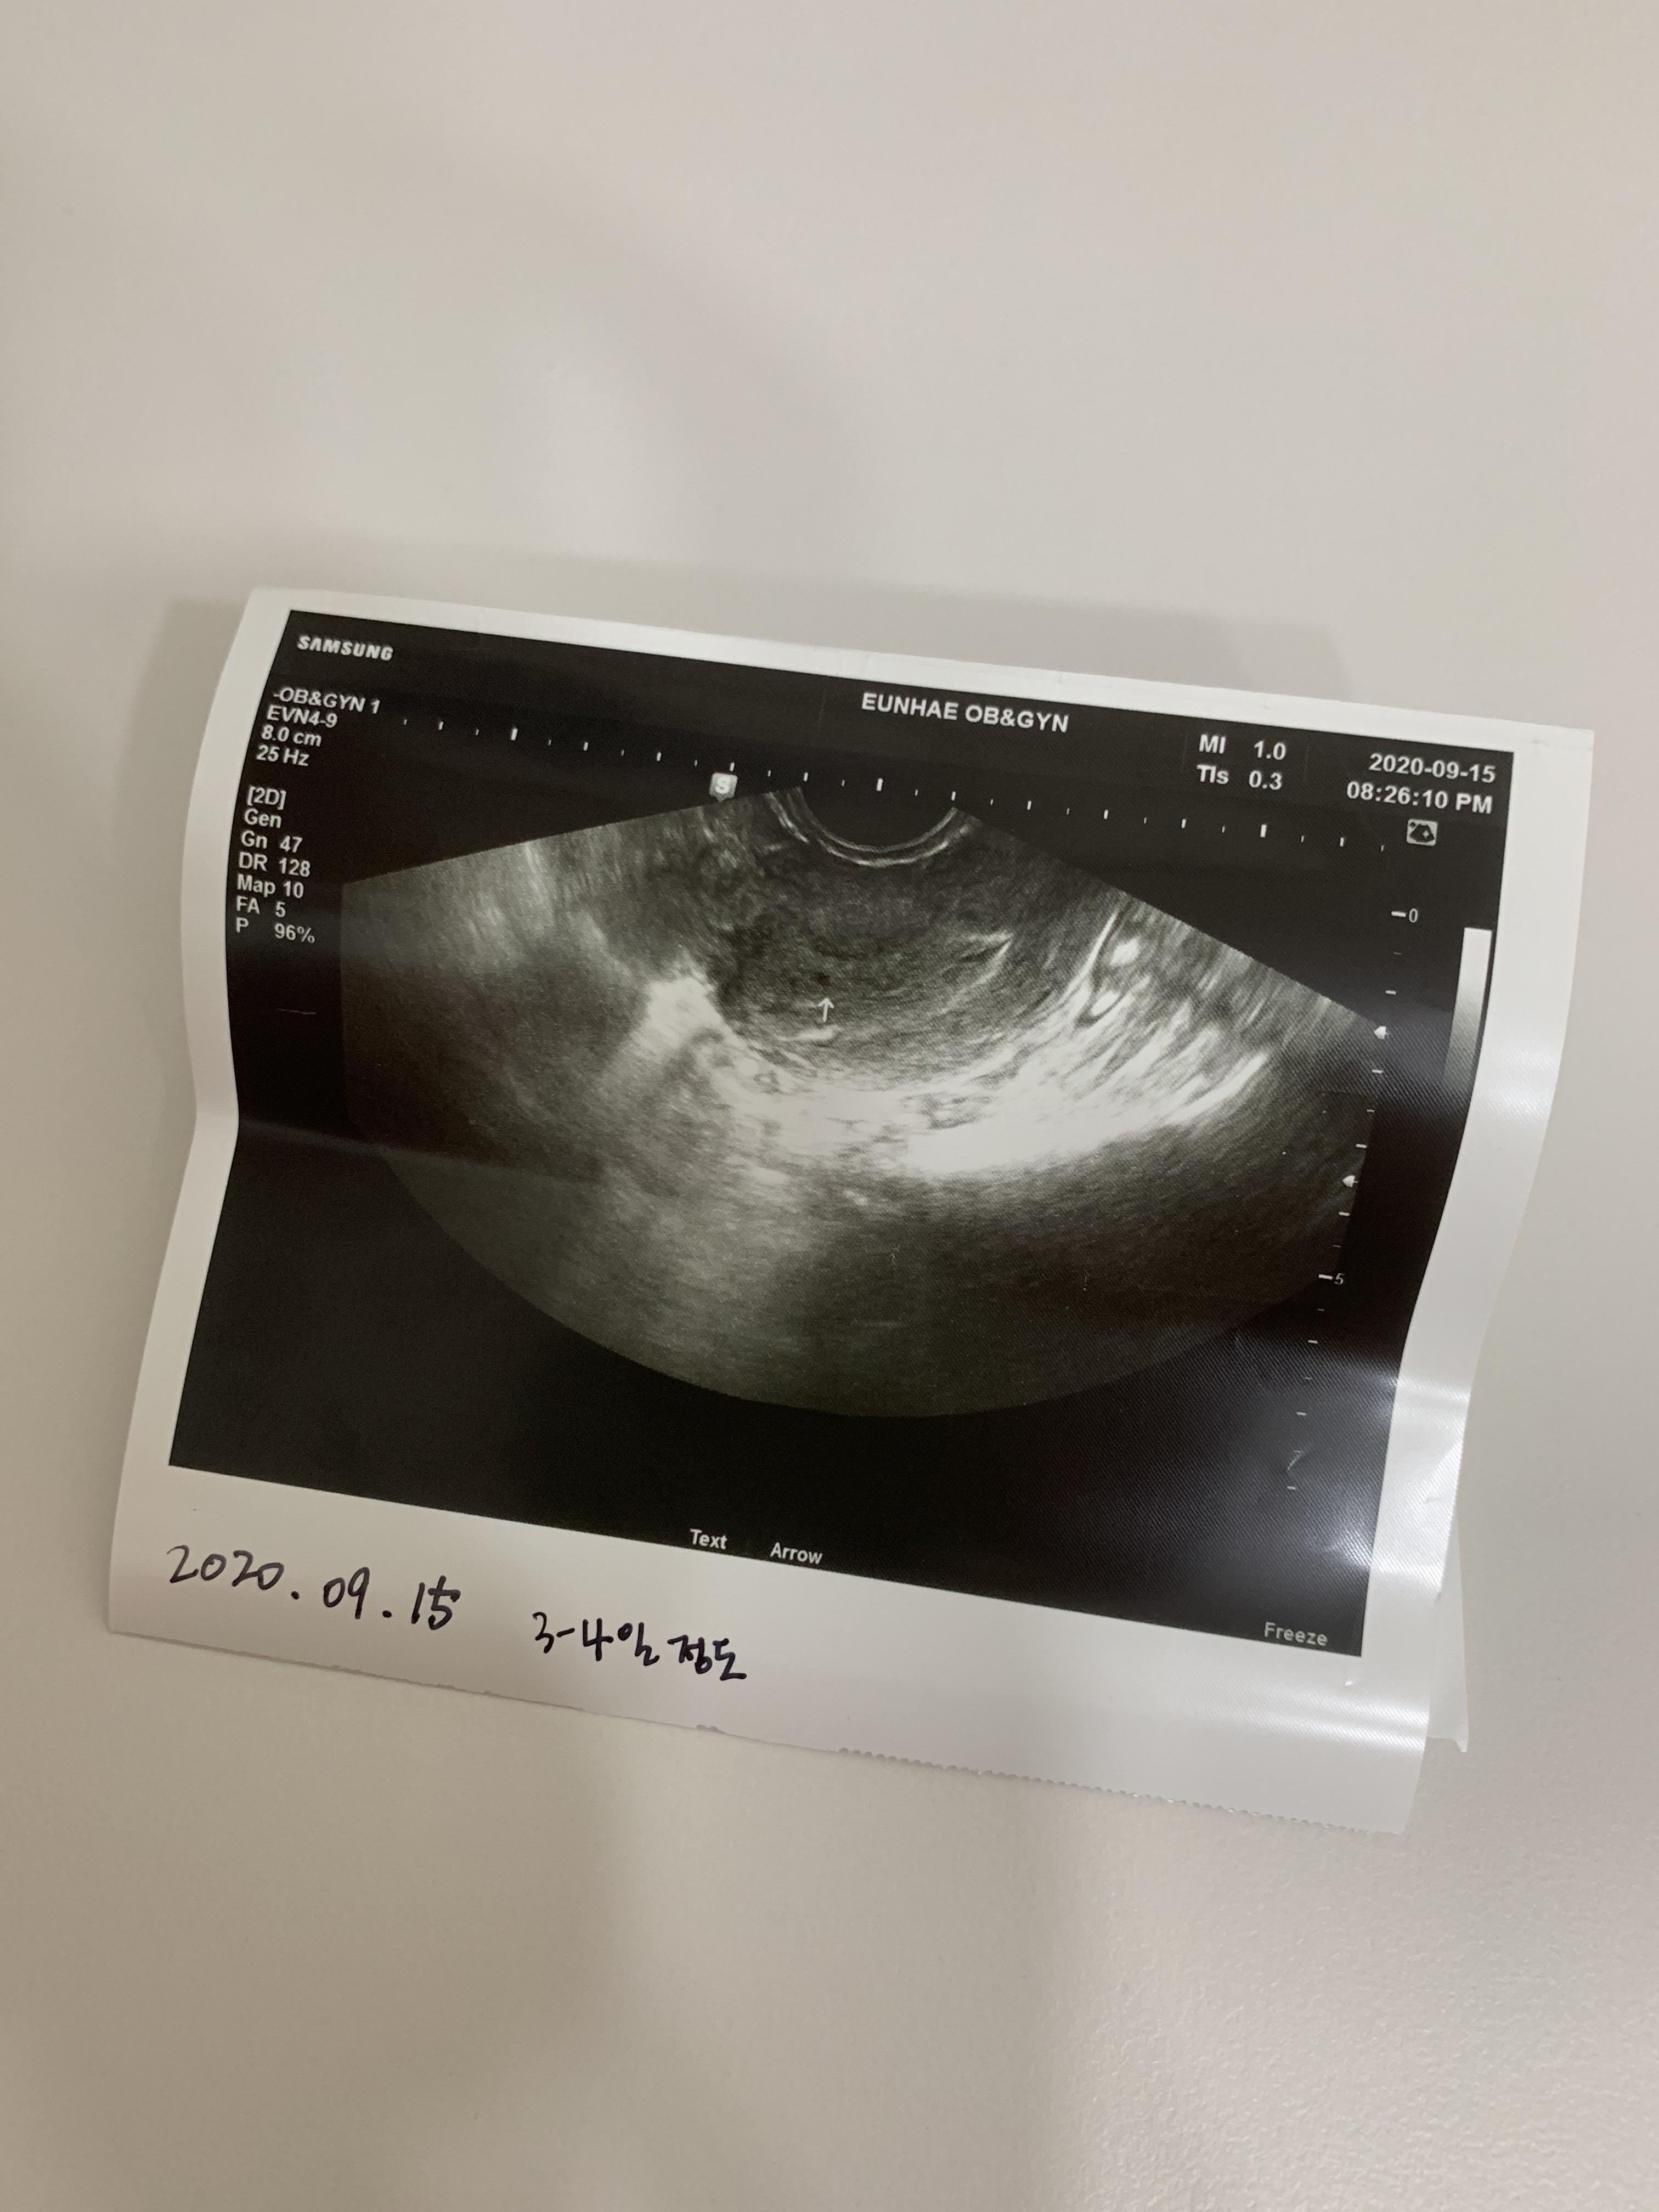

8월에 본격적으로 일본어 공부를 하다가 구몬회화 수업을 시작하게 되었어요 8월 11일부터 오봉(일본의 중추절)때 집 청소도 같이 하고 공원도 가고 달리기도 하고 크로스도 하고 -시골, 그리고 8월에 함께 저녁을 먹었습니다. 먹고 마시고 즐기세요. 보내고 있는데 8월 24일 생리예정일이 지나고 임신테스트기로 4주차에 임신했어요

처음에는 제가 임신했다는 사실이 믿기지 않았고 병원에서 6주에 첫 내원을 예약해 놓았지만 조금 불안했고 무리하지 않으려고 노력했습니다.